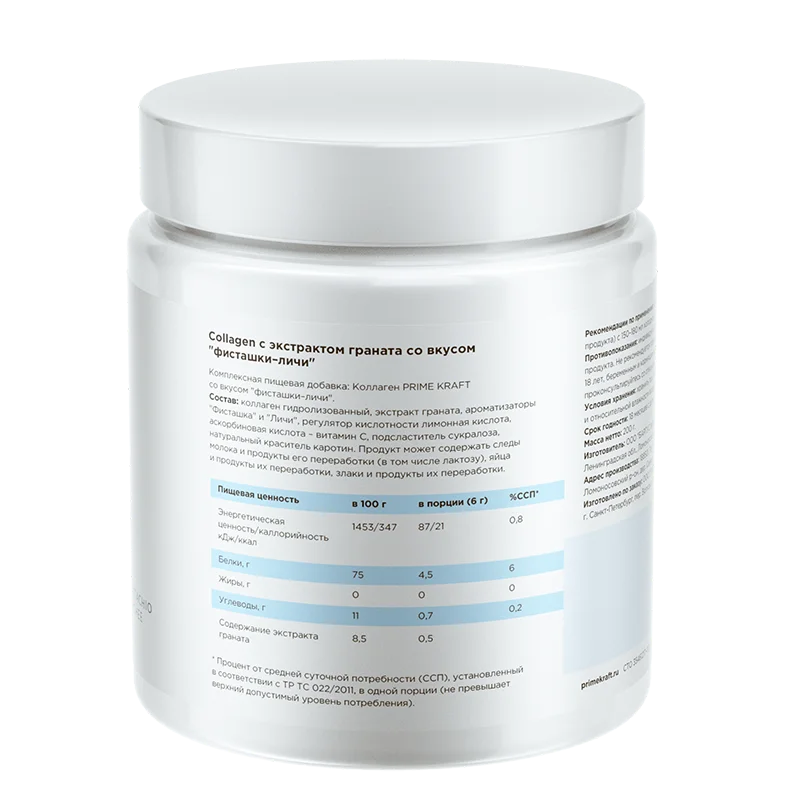

Коллаген от Prime Kraft – гидролизованный говяжий I-го типа, дополнительно обогащен витамином С, которая улучшает его усвояемость в организме, и экстрактом граната – природным антиоксидантом, который содержит удивительный набор из 15 аминокислот, причем 6 из них есть только в мясе и для растительной пищи уникальны!

Принимать коллаген от Prime Kraft рекомендуется 1 раз в день для профилактики, для активной поддержки восстановления суставов – 2 раза в день. Для этого надо смешать 1 мерную ложку (6 г сухого продукта) с 150-180 мл холодной питьевой воды в стакане или шейкере – не смешивая с приемами пищи и тем более протеином.